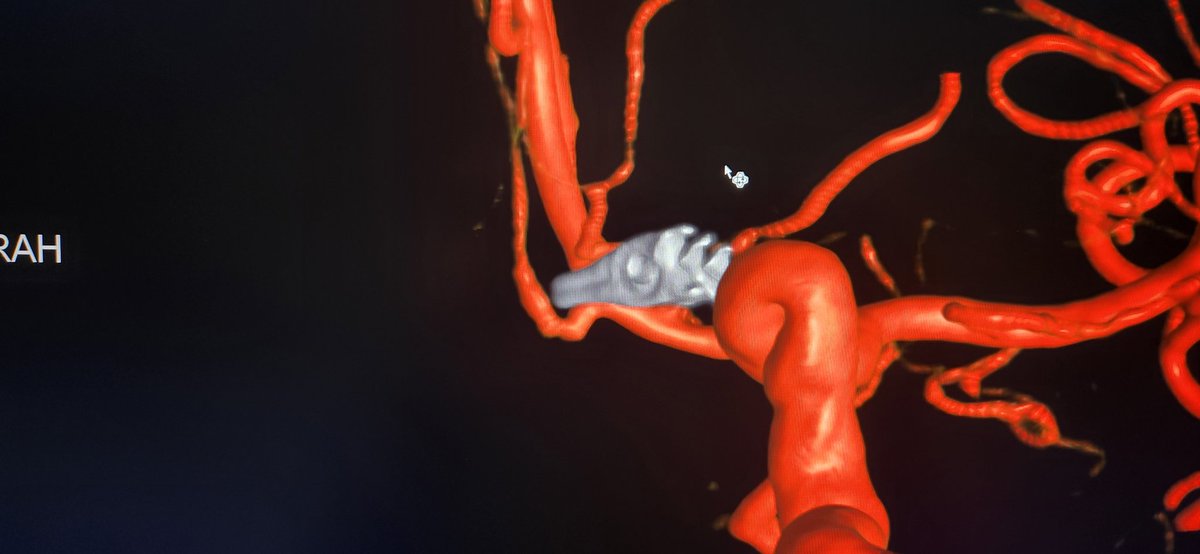

Ruptured. Curable with embolization alone? I presented this case at Sun Valley Cerebrovascular Conference & many skeptics spoke up. Just performed 2nd control angio 1.5 yr later with no trace of lesion. #avm #embolization #embocure #radial #neurointervention @StLukesHealth

@EAMDMD

Edward Duckworth, MD, MS

3 years

Would you have treated differently? Let's talk about it at the @SunValleyCVConf Jan 19-21 at beautiful @sunvalley resort #idaho. #skiing #snowboarding @StLukesHealth @UCSDNeuroSurg @MemphisNSGY Conference details